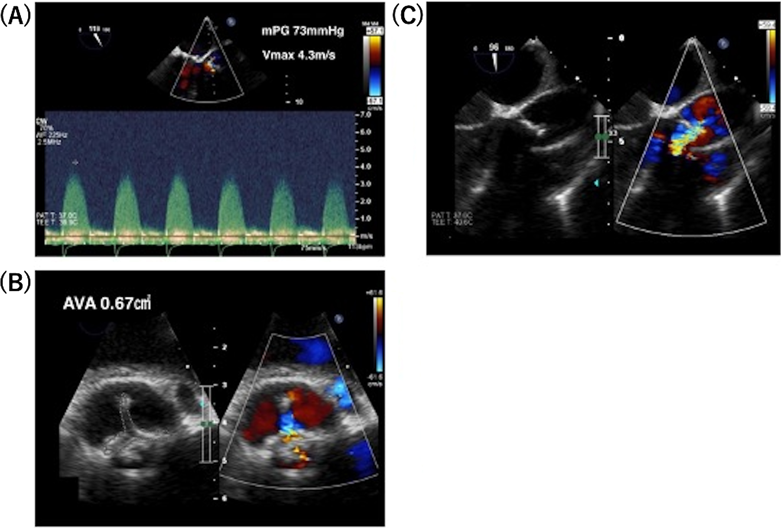

心電図のST-T変化とトロポニンT上昇を認めていたことから急性心筋炎の可能性も考慮し,小児集中治療室へ入室となった.低血圧やST-T変化が持続していたため,経口挿管と全身麻酔の上,経食道心臓超音波検査(transesophageal echocardiography: TEE)と心臓カテーテル検査を実施した.TEEでは,収縮期血圧50~70 mmHgの条件下で,大動脈弁平均圧較差は73 mmHg,大動脈弁最大血流速度4.3 m/sec,大動脈弁開口面積は0.67 cm2と重症大動脈弁狭窄の所見であった(Fig. 4).心臓カテーテル検査では,大動脈圧75/59(平均64)mmHg,肺動脈圧64/39(50)mmHg,肺毛細血管楔入圧38 mmHg,右室圧62/9(拡張末期圧13)mmHgであった.再度の大動脈弁基部置換術を要すると判断し,手術可能な施設に転院した.

Pediatric Cardiology and Cardiac Surgery 41(2): 91-96 (2025)

Fig. 4 Transesophageal echocardiography on admission

The mean aortic valve pressure gradient (mPG) was 73 mmHg, the maximum aortic valve velocity (Vmax) was 4.3 m/sec (A), and the aortic valve area (AVA) was 0.67 cm2 (B). The aortic regurgitation was moderate (C).